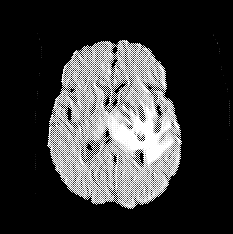

We introduce a neural network framework, utilizing adversarial learning to partition an image into two cuts, with one cut falling into a reference distribution provided by the user. This concept tackles the task of unsupervised anomaly segmentation, which has attracted increasing attention in recent years due to their broad applications in tasks with unlabelled data. This Adversarial-based Selective Cutting network (ASC-Net) bridges the two domains of cluster-based deep learning methods and adversarial-based anomaly/novelty detection algorithms. We evaluate this unsupervised learning model on BraTS brain tumor segmentation, LiTS liver lesion segmentation, and MS-SEG2015 segmentation tasks. Compared to existing methods like the AnoGAN family, our model demonstrates tremendous performance gains in unsupervised anomaly segmentation tasks. Although there is still room to further improve performance compared to supervised learning algorithms, the promising experimental results shed light on building an unsupervised learning algorithm using user-defined knowledge.